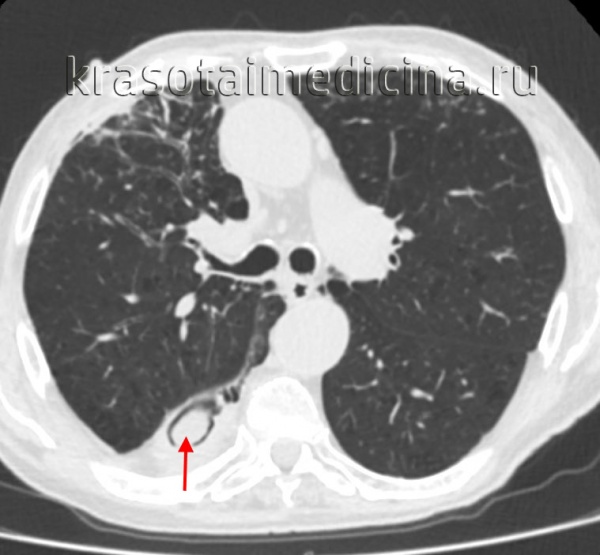

(Слева) На аксиальной КТ без КУ у женщины 61 года с острой идиопатической эозинофильной пневмонией определяются диффузные участки «матового стекла» на фоне утолщения междольковых перегородок и внутридольковых тяжей. Это т.н. картина «сумасшедшей исчерченности».

(Справа) На корональной КТ без КУ у этой же пациентки определяются диффузные двусторонние участки «матового стекла». Острая эозинофильная пневмония характеризуется быстрым возникновением дыхательной недостаточности, лихорадки и эозинофилии, и связана с недавним началом курения или вдыханием пыли во время терактов во Всемирном Торговом Центре.

• ОЭП:

о «Матовое стекло» (100%), картина «сумасшедшей исчерченности», «мозаичная» картина

о Утолщение междольковых перегородок в отсутствие узлов (90%)

о Утолщение бронховаскулярных пучков (66%)

о Консолидация (55%)

о Центрилобулярные очаги с нечеткими границами (30%)